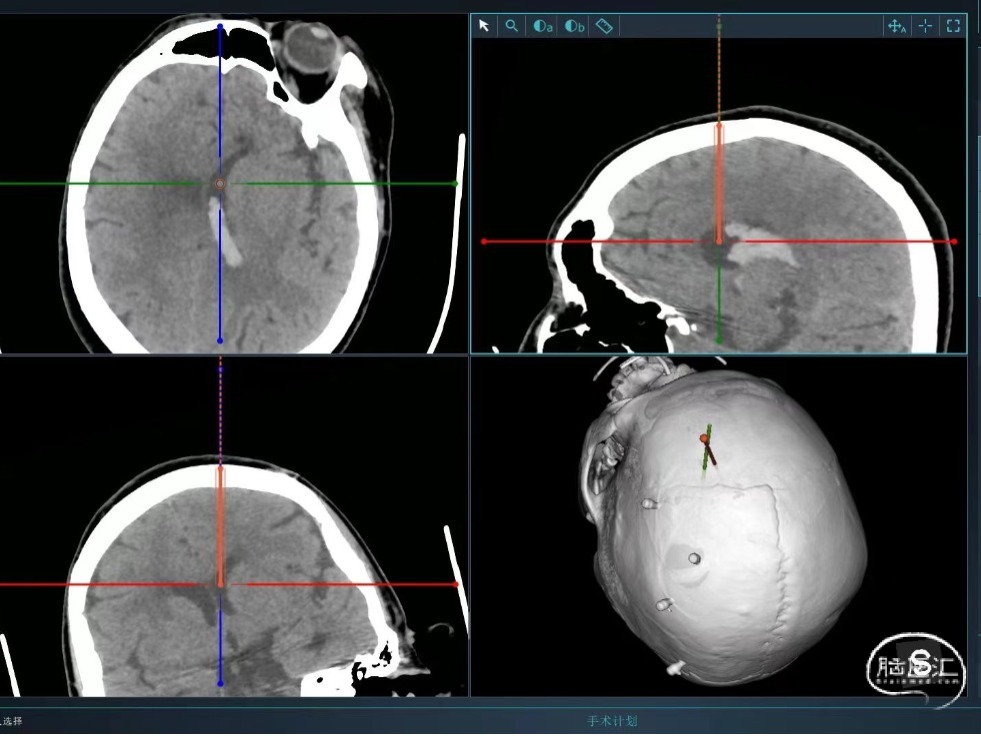

既往史:患者于入院前3小时工作时无明显原因及诱因出现右侧肢体无力,伴短暂意识丧失,随后患者呈嗜睡状,无恶心、呕吐,经短暂休息后,未见好转,经120送入我院急诊,急诊行头颅CT示:左侧丘脑出血破入脑室,出血量约为20ml。

辅助检查:头颅CT(我院):右侧丘脑出血破入脑室,出血量约20ml。

术前

Pre-op

术中

一孔两管